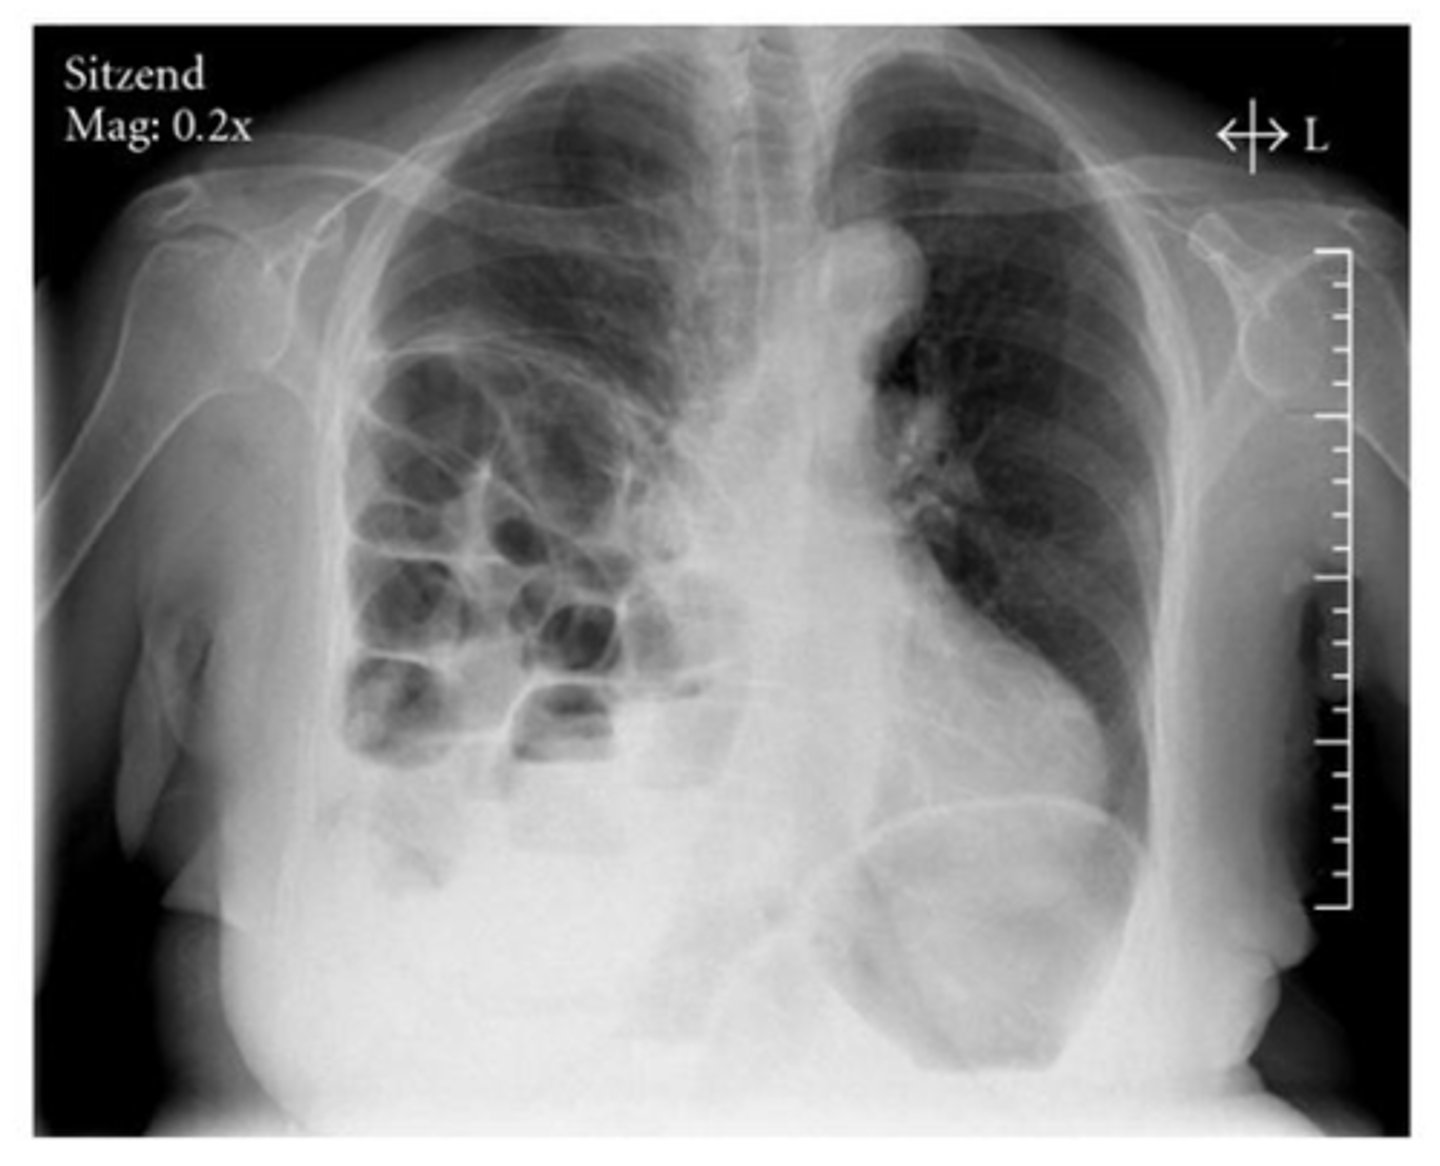

Moderate CHF with:

-redistribution of pulmonary vasculature (pulm vasculature should not be visible at all, esp in apices, but they are visible here)

-cardiomegaly and L sided pleural effusion

Mild to moderate CHF with redistribution of pulmonary vasculature, indistinct hila, mild cardiomegaly and Kerley B lines.

What signs on radiograph indicate CHF?